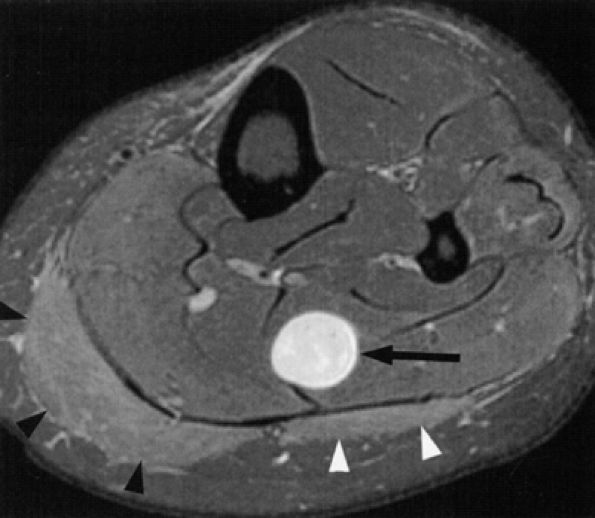

FIGURE 6.3 ● Proximal tibial entrapment in a 49-year-old patient with neuropathic foot pain. Symptoms resolved following an intra-articular steroid injection of the knee. This axial T2-weighted fat-suppressed image depicts a loose body in the popliteal muscle bursa (arrow), abutting on the neurovascular structures (arrowheads).There are many variations in muscle innervation and many communicating nerve loops in the lower extremity, particularly in the foot region.43 For example, the deep peroneal nerve may, in rare instances, supply muscles such as the adductor hallucis and flexor hallucis brevis, muscles typically innervated by the lateral and medial plantar nerves. This variability can affect the distribution of signal alterations within denervated muscles and may produce puzzling MR patterns. Familiarity with variations in innervation aids in interpreting unexpected muscle denervation signal alterations. -

Finally, the distance from the site of entrapment to the innervated muscle should be considered when searching for muscle denervation abnormalities. Proximal damage to the peroneal division of the sciatic nerve may depict denervation signal in the leg or foot. This signal alteration may be missed if only the thigh is being imaged. Similarly, MR imaging of a painful foot may overlook a more proximal entrapment in the leg or thigh (Fig. 6.3). It is important to pay careful attention to signal changes on sagittal and coronal planes, where larger portions of the limb are illustrated, to help avoid this pitfall. If the clinical suspicion for entrapment is high and no abnormalities are noted on the initial study, imaging a more distal or proximal section of the limb can also be performed.